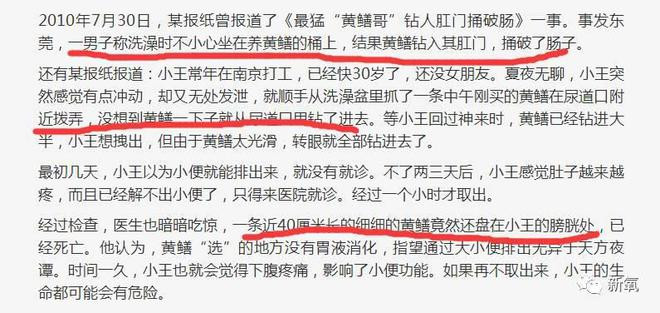

第三:那些手术的图片是以前的新闻,是一个男的生吃鳝鱼,钻到内脏里的手术图。

因为这事件之前就有过,一男子将5条泥鳅和1条黄鳝塞入肚中,只为追求刺激,这货是在拿生命开玩笑啊。

这边还有一个浙江的医生见过一男子将泥鳅和黄鳝塞入肛门,结果搞得痛不欲生来到医院救治的。国外还真有一男子直播生吞黄鳝,最后好像是真死了,no zuo no die why you try?

医生科普:塞入肛门的泥鳅和黄鳝之类活物,会垂死挣扎,钻破肠道。临床上见到,多是钻破乙状结肠,如不及时手术,病人必死无疑。而动手术,由于腹腔被大便所污染,也必须分两步做。首先做结肠造瘘,乙状结肠修补,待病情允许,几个月后再接回肠子。病人即使能捡回一条命,也是痛不欲生,会留下不少后遗症。

关于黄鳝的迷死氧随手一查,尼玛也太多极端的人了,有无意的有故意的,但是毫无疑问都很危险。有医治好的,有死亡的。

一哥们洗澡时不小心被捅破了肠子,网友称打开了新世界的大门。

X光照片中黄鳝大逃亡,显然是在疯狂找出口。